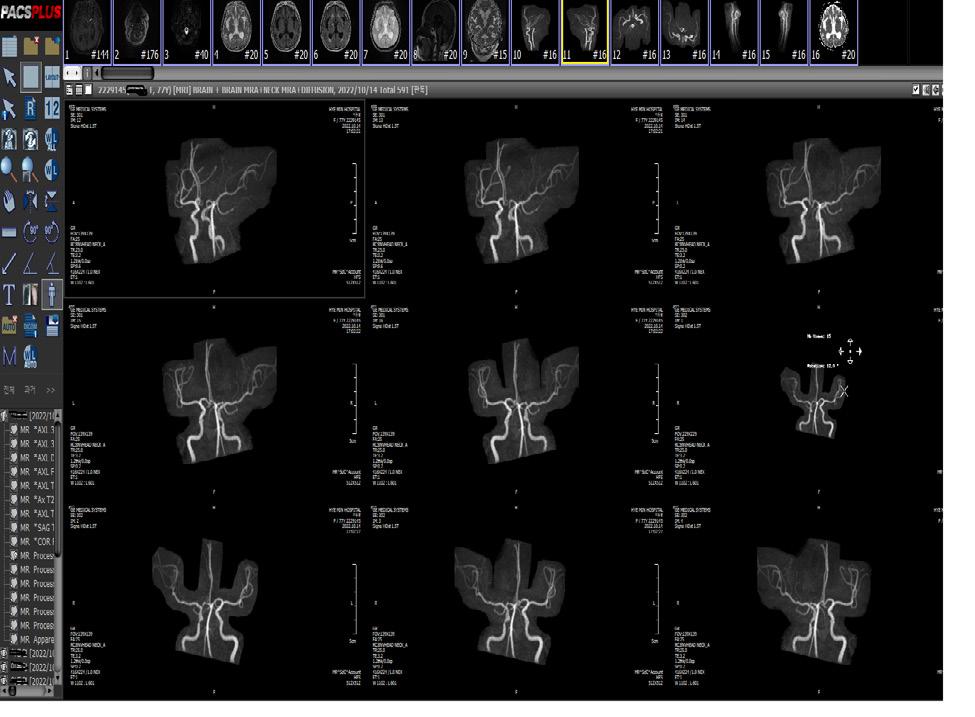

์ฝ”๋กœ๋‚˜19 ๊ฐ์—ผ๊ฒฝ๋กœ

๊ฐ์—ผ๋œ ์‚ฌ๋žŒ์˜ ๋น„๋ง์„ ํ†ตํ•œ ์‚ฌ๋žŒ ๊ฐ„ ์ „ํŒŒ๊ฐ€ ๊ธฐ๋ณธ ๊ฒฝ๋กœ๋กœ, ํ˜ธํก์„ ํ†ตํ•ด ๊ฐ์—ผ๋œ ์‚ฌ๋žŒ์˜ ๋น„๋ง์„ ์ง์ ‘ ๋“ค์ด๋งˆ์‹œ๊ฑฐ๋‚˜, ๊ฐ์—ผ๋œ ์‚ฌ๋žŒ์˜ ๋น„

๋ง์ด ๋ˆˆ, ์ฝ”, ์ž…์˜ ์ ๋ง‰์— ํŠ€์–ด ๋ฌป๊ฑฐ๋‚˜, ํ‘œ๋ฉด์— ๋–จ์–ด์ง„ ๋ณ‘์›์ฒด๋ฅผ ํฌํ•จ ํ•œ ๋น„๋ง์„ ์†์œผ๋กœ ๋งŒ์ง„ ํ›„ ๋ˆˆ, ์ฝ”, ์ž…์„ ๋งŒ์ง€๋Š” ํ‘œ๋ฉด ์ ‘์ด‰์— ์˜

ํ•ด ์ „ํŒŒ๋  ์ˆ˜ ์žˆ๊ณ , ๊ฐ์—ผ๋œ ์‚ฌ๋žŒ์—๊ฒŒ ๊ธฐ๊ด€์ง€ ๋‚ด์‹œ๊ฒฝ ๊ฒ€์‚ฌ, ๊ฐ๋‹ด ์œ ๋„, ๊ธฐ๊ด€ ์‚ฝ๊ด€, ์‹ฌํ์†Œ์ƒ์ˆ  ๋“ฑ์„ ์‹œํ–‰ํ•˜์—ฌ ์—์–ด๋กœ์กธ์„ ๋ฐœ์ƒํ•˜๊ฑฐ๋‚˜

ํ™˜๊ธฐ๊ฐ€ ๋ถ€์ ์ ˆํ•œ ๋ฐ€ํ๋œ ๊ณต๊ฐ„์—์„œ ๊ฐ์—ผ์ž์™€ ๋˜๋Š” ๊ฐ์—ผ์ž๊ฐ€ ์žฅ๊ธฐ๊ฐ„ ๋จธ๋ฌธ ๋’ค ๋– ๋‚œ ์งํ›„ ๋ฐฉ๋ฌธํ•œ ๊ฒฝ์šฐ์˜ ๊ณต๊ธฐ์ „ํŒŒ๊ฐ€ ์žˆ์œผ๋ฉฐ ์ตœ๊ทผ ์—ฐ๊ตฌ ๊ฒฐ๊ณผ์— ๋”ฐ๋ฅด๋ฉด ๊ณต๊ธฐ์ „ํŒŒ์˜ ๊ฐ€๋Šฅ์„ฑ์„ ์ข€ ๋” ๋†’๊ฒŒ ๋ณด๊ณ  ์žˆ๋‹ค.